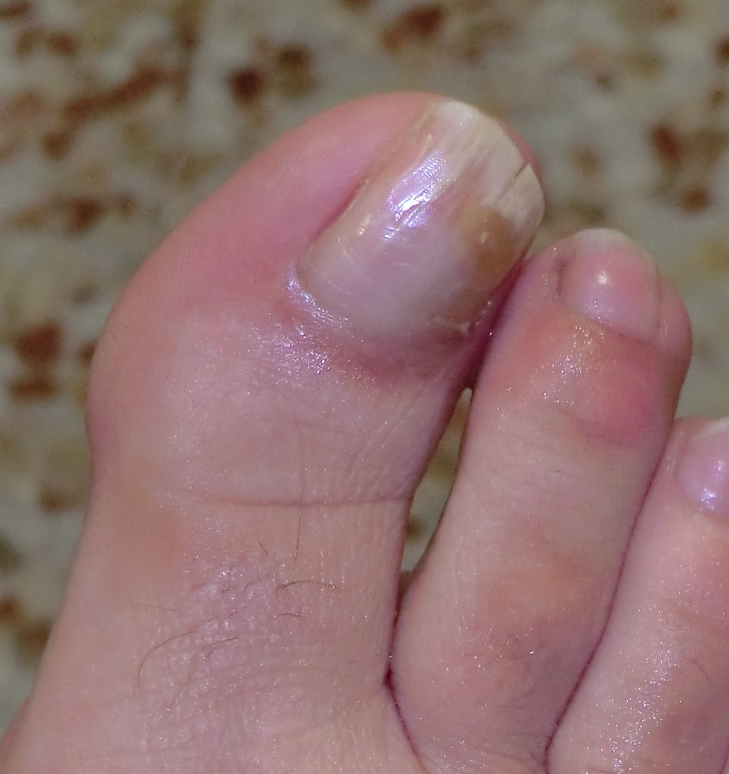

Ante un cambio en la forma y coloración de la uñas, lo primero que pensamos es que puedan ser «hongos» pero en la gran mayoría de los casos el problema está «en el interior». La uña está engrosada, puede tener alguna grieta, cambio de color y además puede ser dolorosa a la presión del calzado. Ese aspecto de «uña fea» puede ser a consecuencia de la malformación o del mal crecimiento del hueso que hay en el interior del dedo y que da lugar a esta malformación de la uña debido a que este hueso invade el territorio de todo el aparato ungueal. Digamos que la uña en vez de crecer normalmente a lo largo (longitudinalmente) crece a lo alto (verticalmente) dando ese aspecto de «uña enferma». Por ello, para un buen diagnóstico es necesario un estudio radiológico donde poder observar esa excrecencia de hueso que dará lugar a ese mal crecimiento de la uña. Las imágenes radiológicas nos van a mostrar ese montículo en el hueso causante de la deformidad de la uña.